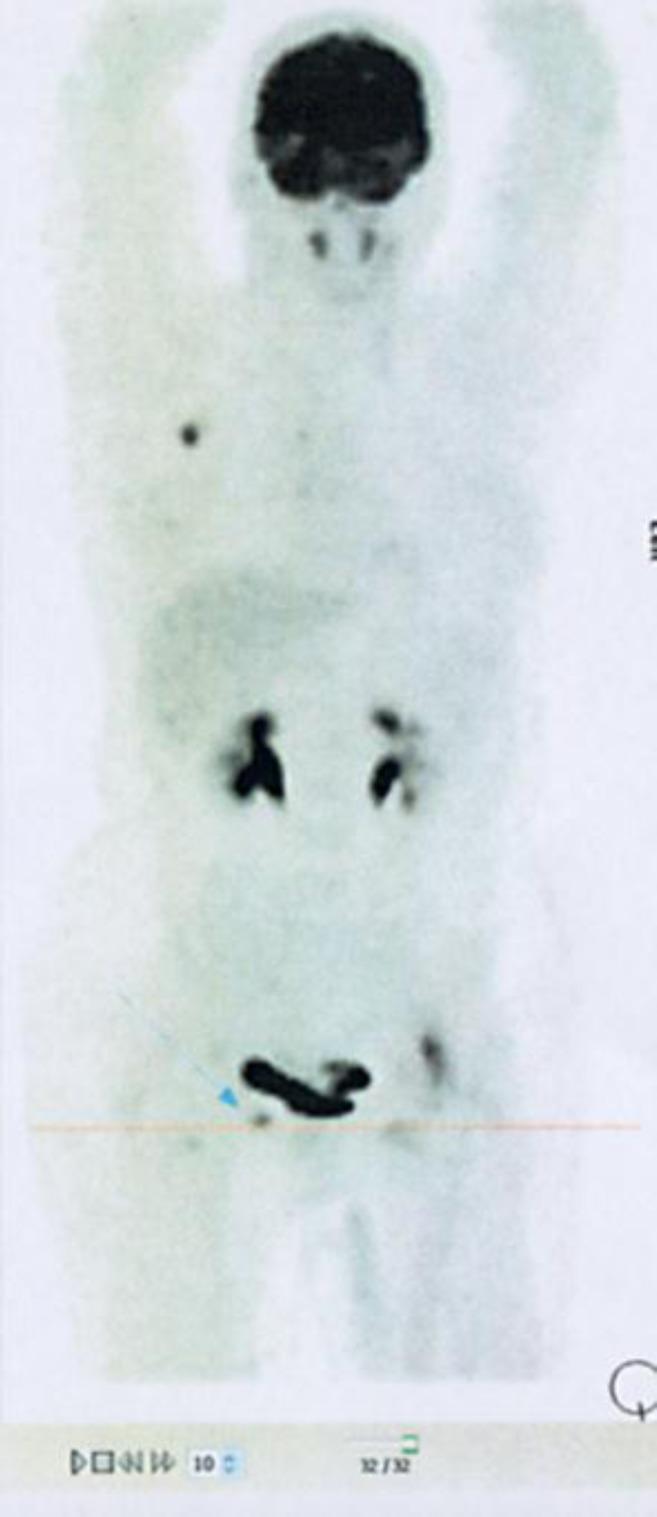

A 42-year-old, premenopausal woman presented with facial paralysis on the central left side accompanied by a left tongue deviation, an upward vertical nystagmus, moderate spastic paraparesis, dystonic posturing of the left foot, lower limb hyperreflexia and bilateral extensor plantar reflex. After ruling out all other potential neurologic causes, PNS was suspected but no ONAs were found. A PET-CT scan detected increased metabolism in the right breast, as well as an ipsilateral thoracic interpectoral adenopathy. Core biopsy confirmed the presence of an infiltrating duct carcinoma. After breast surgery, the neurologic symptoms disappeared. One week later, the patient was readmitted to the hospital with a bilateral fatigable eyelid ptosis, and two weeks later, there was a noticeable improvement in eyelid ptosis, accompanied by a rapid and progressive development of lower spastic paraparesis. She started adjuvant treatment with chemotherapy with marked clinical and neurological improvement, and by the end of radiotherapy, there were no signs of neurologic impairment.

一名42岁的绝经前女性出现左侧中枢性面瘫,伴有左侧舌偏斜、向上垂直性眼球震颤、中度痉挛性截瘫、左脚肌张力障碍姿势、下肢反射亢进和双侧巴宾斯基征阳性。排除所有其他潜在的神经病因后,怀疑为PNS,但未发现ONA。PET-CT扫描显示右乳代谢增加,同侧胸肌间淋巴结肿大。芯针活检证实存在浸润性导管癌。乳腺手术后,神经症状消失。一周后,患者因双侧可疲劳性眼睑下垂再次入院,两周后,眼睑下垂有明显改善,同时下半身痉挛性截瘫迅速进展。她开始接受辅助化疗,临床和神经症状均有明显改善,放疗结束时,无神经功能损害迹象。